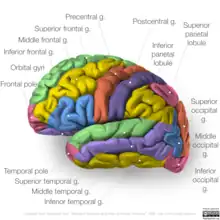

The occipital lobe is divided into several functional visual areas. Each visual area contains a full map of the visual world. Although there are no anatomical markers distinguishing these areas (except for the prominent striations in the striate cortex), physiologists have used electrode recordings to divide the cortex into different functional regions.

The first functional area is the primary visual cortex. It contains a low-level description of the local orientation, spatial-frequency and color properties within small receptive fields. Primary visual cortex projects to the occipital areas of the ventral stream (visual area V2 and visual area V4), and the occipital areas of the dorsal stream—visual area V3, visual area MT (V5), and the dorsomedial area (DM).

A significant functional aspect of the occipital lobe is that it contains the primary visual cortex.

Retinal sensors convey stimuli through the optic tracts to the lateral geniculate bodies, where optic radiations continue to the visual cortex. Each visual cortex receives raw sensory information from the outside half of the retina on the same side of the head and from the inside half of the retina on the other side of the head. The cuneus (Brodmann's area 17) receives visual information from the contralateral superior retina representing the inferior visual field. The lingula receives information from the contralateral inferior retina representing the superior visual field. The retinal inputs pass through a "way station" in the lateral geniculate nucleus of the thalamus before projecting to the cortex. Cells on the posterior aspect of the occipital lobes' gray matter are arranged as a spatial map of the retinal field. Functional neuroimaging reveals similar patterns of response in cortical tissue of the lobes when the retinal fields are exposed to a strong pattern.

If one occipital lobe is damaged, the result can be homonymous hemianopsia vision loss from similarly positioned "field cuts" in each eye. Occipital lesions can cause visual hallucinations. Lesions in the parietal-temporal-occipital association area are associated with color agnosia, movement agnosia, and agraphia. Lesions near the left occipital lobe can result in pure alexia (alexia without agraphia). Damage to the primary visual cortex, which is located on the surface of the posterior occipital lobe, can cause blindness due to the holes in the visual map on the surface of the visual cortex that resulted from the lesions.[5]